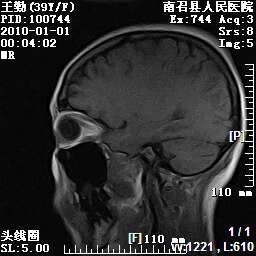

以下是引用随光逐影在2010-1-22 9:03:00的发言:[br]考虑左侧中颅窝(蝶骨翼区)脑膜瘤侵犯蝶骨翼并突入左侧眼眶。

以下是引用水过无痕在2010-1-22 14:55:00的发言:[br]一、定位:颅外占位;二、定性:恶性可能性大;三、组织来源:来源于左侧眼外直肌或其他部位;考虑为:横纹肌肉瘤>转移瘤>脑膜瘤.